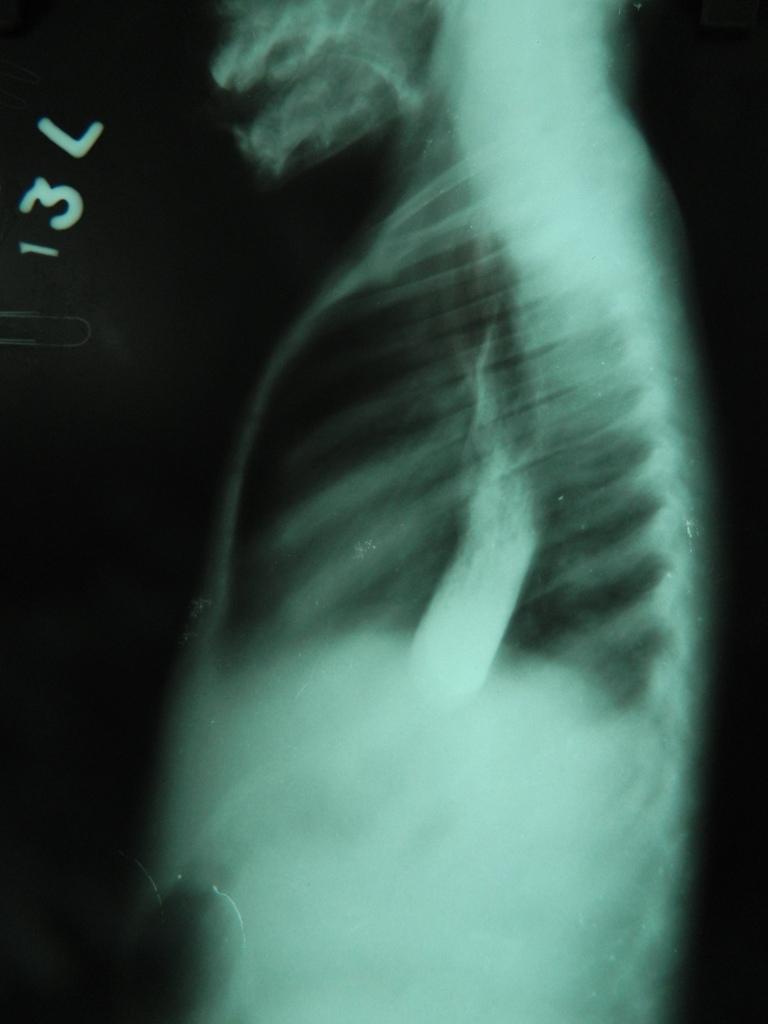

Achalasia cardia is a neuromuscular disorder of unknown etiology involving the body of the esophagus and lower esophageal sphincter (LES). It is characterized by aperistalsis of the body of the esophagus and failure of relaxation of lower esophageal sphincter. It usually affects patients between the ages of 30 and 60 years. It is unusual in childhood and extremely rare in infants. We report two cases of achalasia cardia in infants. Both cases were treated with open Heller's esophagocardiomyotomy with anti-reflux procedure.

https://cdn.ncbi.nlm.nih.gov/pmc/blobs/0726/3708635/abc26a439d59/JIMA-44-1-09260-g001.jpg